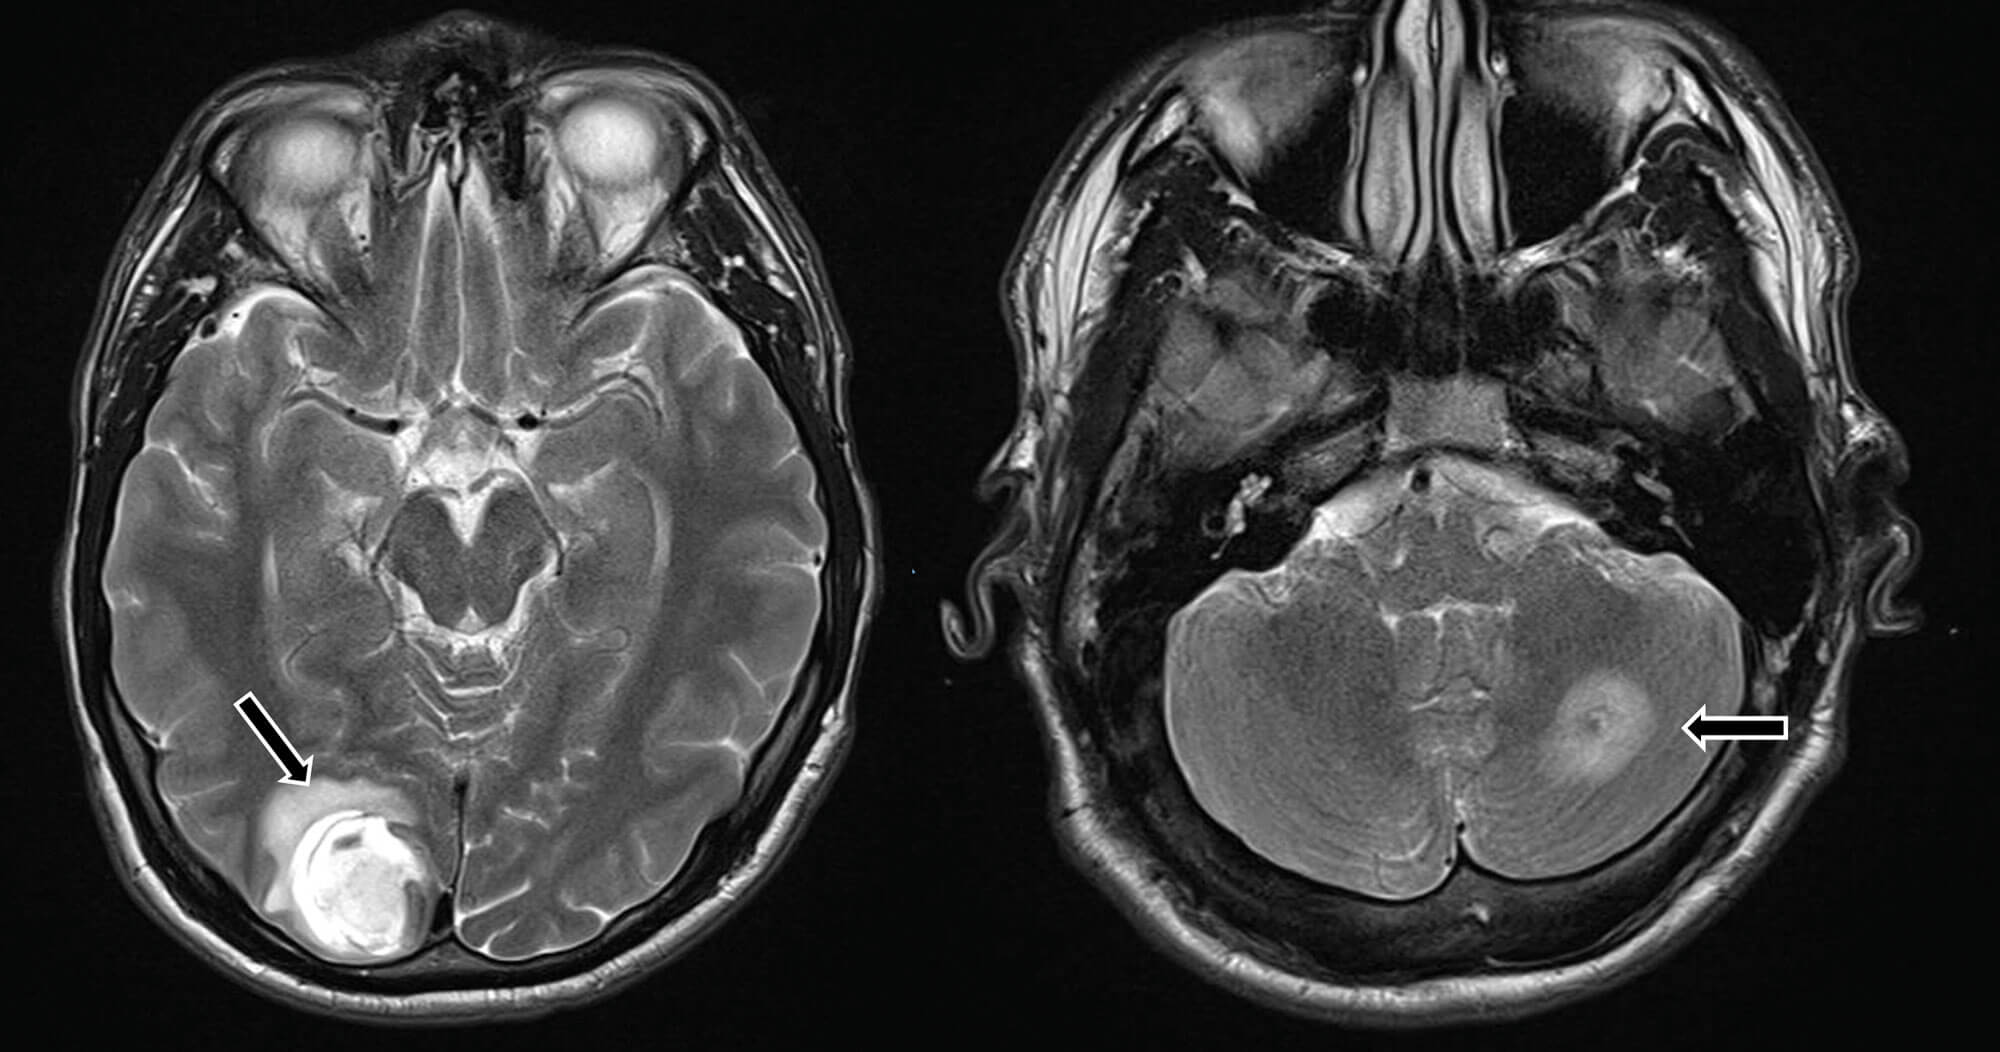

He represented five months later when he collapsed at home with seizures and a reduced Glasgow Coma Scale (GCS). On further questioning, he reported headaches for the past 11 weeks and poor vision from his left eye. An MRI brain showed a haemorrhagic lesion in the occipital lobe and multiple ring-enhancing lesions in the cerebrum and cerebellum suspicious for brain metastases (Figure 5).

Figure 5: Haemorrhagic lesion in the right occipital lobe and ring enhancing lesion in the cerebellum, suspicious for metastases.